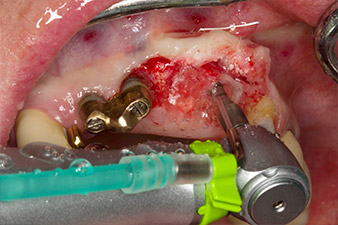

Después de la cicatrización primaria, los tejidos blandos se modelaron con ayuda del puente con base reconstruida. Dos meses después, se procedió a la exposición del área con una incisión de la cresta maxilar en sentido ligeramente palatino (figura 2).

El hueso alveolar de la posición 22 resultó tener unas dimensiones suficientes. Las figuras 2 y 4 muestran la preparación del lecho del implante, el corte de rosca y la colocación del implante con el equipo Implantmed.

Para compensar la pérdida de hueso periodontal y conseguir un resultado estético, el implante se combinó con una regeneración ósea guiada con material sustituto xenógeno y con una membrana de colágeno

(figuras 5 y 6).